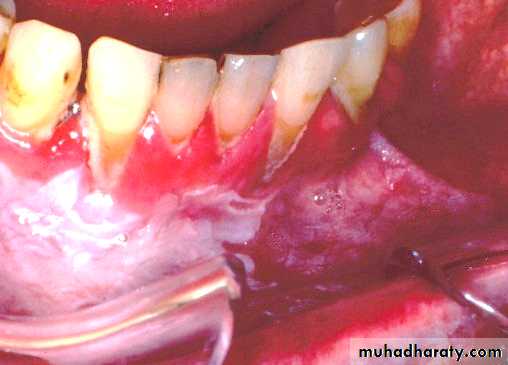

Nicotine stomatitis